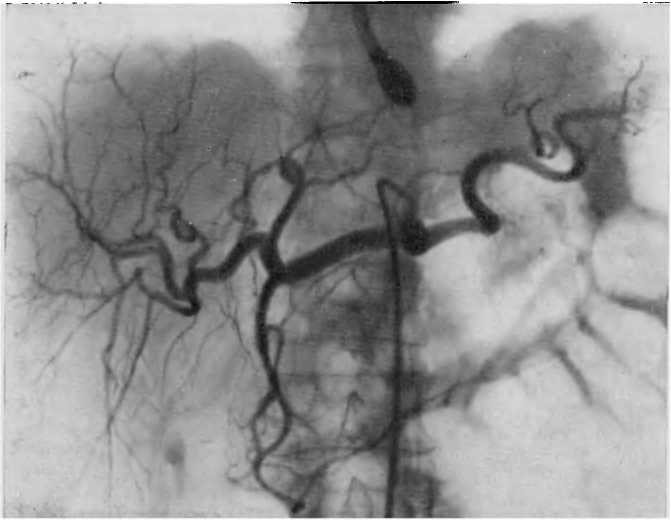

Ангиография висцеральных ветвей аорты

Для тщательного изучения состояния органов, расположенных в брюшной полости, применяется ангиография висцеральных ветвей аорты(сосудов брюшной полости)

Ангиография предполагает введение катетера через бедренную, лучевую либо плечевую артерию. Затем катетер устанавливают в брюшной аорте либо брыжеечных артериях и начинают осуществлять снимки.